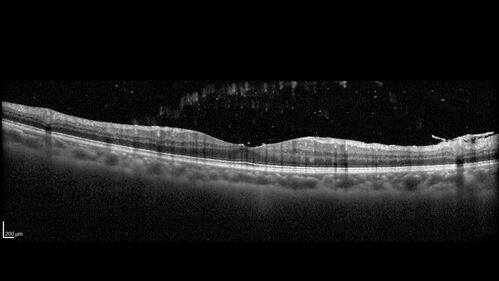

Recurrent Toxoplasmosis Right eye then Left eye 8 years later

33 year old brazilian man. Initially presented with uveitis in the right eye in 2011. Then in the left eye in 2019. Since has had two more episodes.